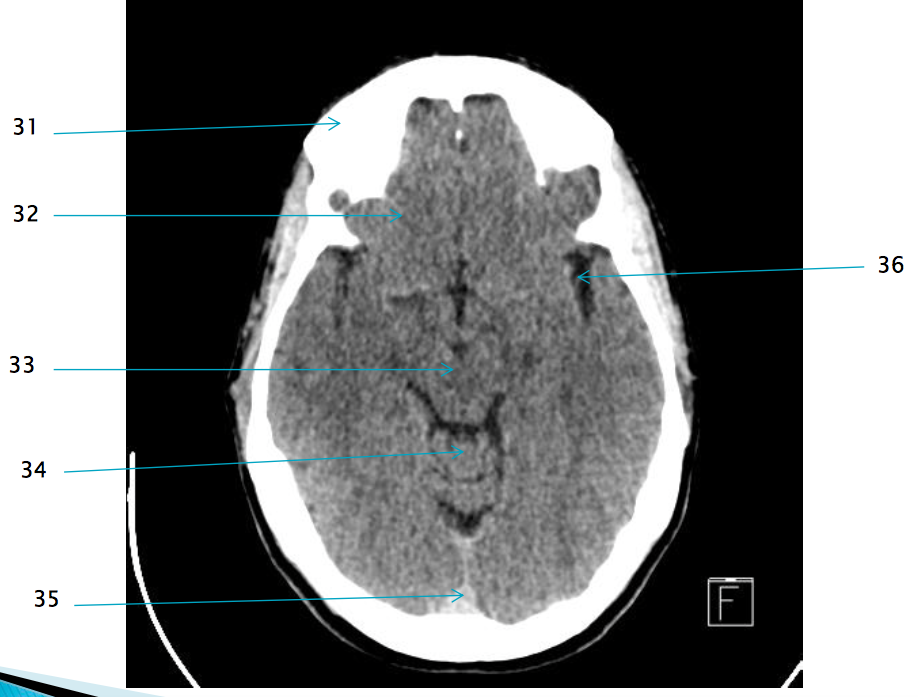

35

Superior sagittal sinus

32

R frontal lobe

37

Frontal horn of R lateral ventricle

19

basilar artery

29

Pre pontine cistern

28

L anterior clinoid process

38

Septum pellucidum